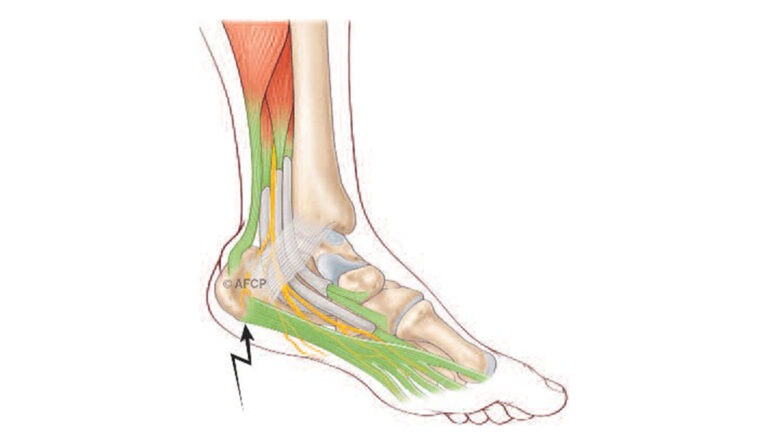

Aponévrosite Plantaire

Aponévrosite Plantaire...

Lire la suite →